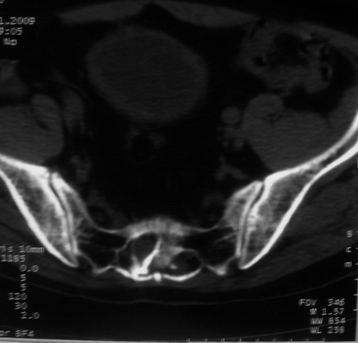

男,85岁,排尿困难。骶椎有问题吗?

1)考虑前列腺增生症并阻塞性膀胱炎。2)骶椎右侧类似囊状骨质密度减低区,边缘骨质硬化,其内为软组织密度影填塞,相邻之骶椎椎管受压变形;考虑为骶椎右侧囊肿或神经纤维瘤。

建议:行mri检查。

骶椎脊索瘤

1)前列腺明显增大,突入膀胱,各叶比例协调,密度均匀,精囊腺及精囊角正常;考虑前列腺增生症并阻塞性膀胱炎。2)骶椎右侧类似囊状骨质密度减低区,边缘骨质硬化,其内为软组织密度影填塞,相邻之骶椎椎管受压变形;考虑为骶椎右侧囊肿或神经纤维瘤。